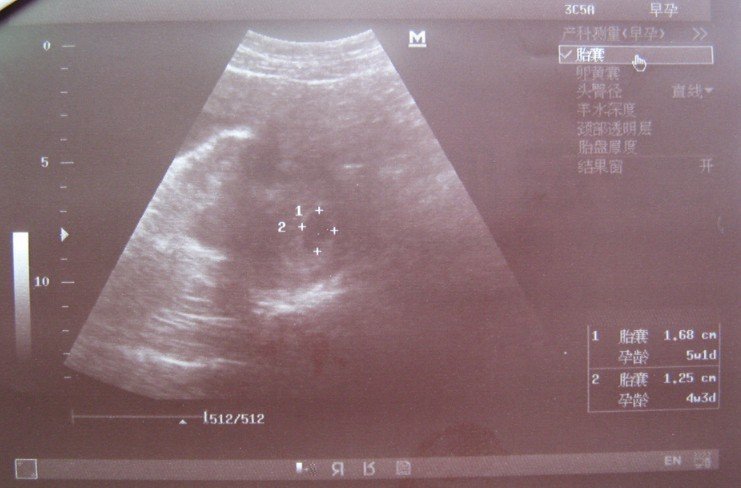

怀孕40天去验血查孕酮和HCG 值,HCG为 71048 mIU/mL,孕酮为 15.710 ng/ml.这两项值有问题吗?

患者信息:女 26岁 想得到怎样的帮助:帮我看看这两项值有问题吗?及彩超单子,分析下我的情况,自己该怎么办?曾经治疗情况及是否有过敏、遗传病史:这是上次流产后3个月再孕